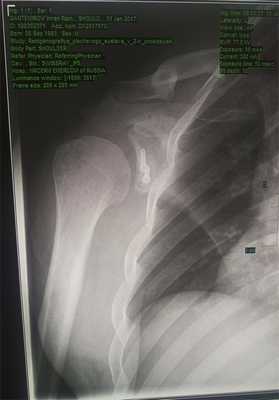

Стандартная рентгенография при нестабильности должна включать исследование в передне-задней проекции в трёх положениях ротации (внутренняя, нейтральная, наружная).